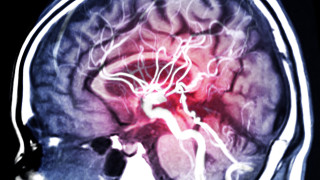

Мозъчния Инсулт - Новини

Днес е световният ден за борба с мозъчния инсулт По